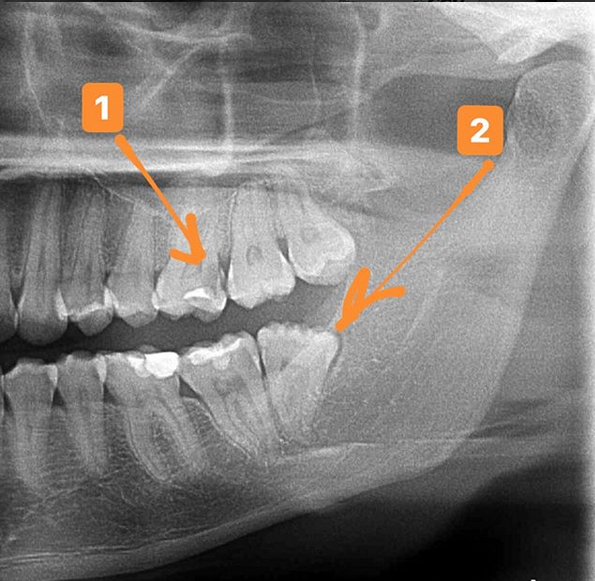

Дентальные снимки и диагностика кариеса